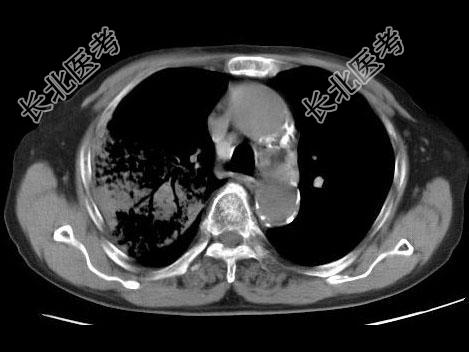

- 单项选择题男,23岁, 高热,咳铁锈色痰, 胸部CT扫描如图,最可能的诊断为 ( )

A、右上肺干酪性肺炎

B、右上肺金葡菌肺炎

C、右上肺大叶性肺炎

D、右上肺中央型肺癌

E、右上肺肺结核